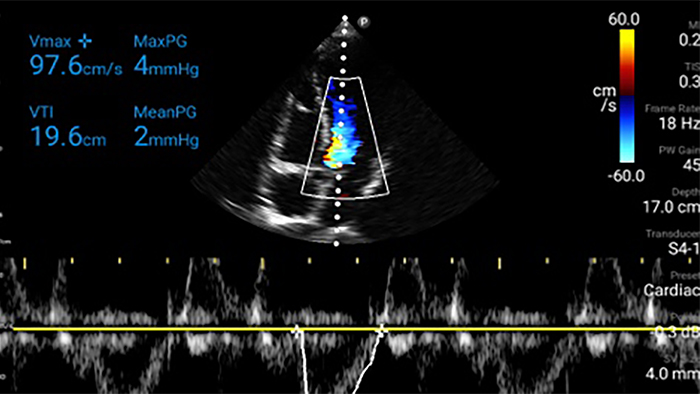

Exceptional ultrasound imaging

Lumify handheld ultrasound offers images that enhance diagnostic confidence.

Lumify can help you make real-time decisions with more confidence, from assessment to recovery. Reveal the subtle details of an image, uncover enriched tissue definition with multiple angles and much more.